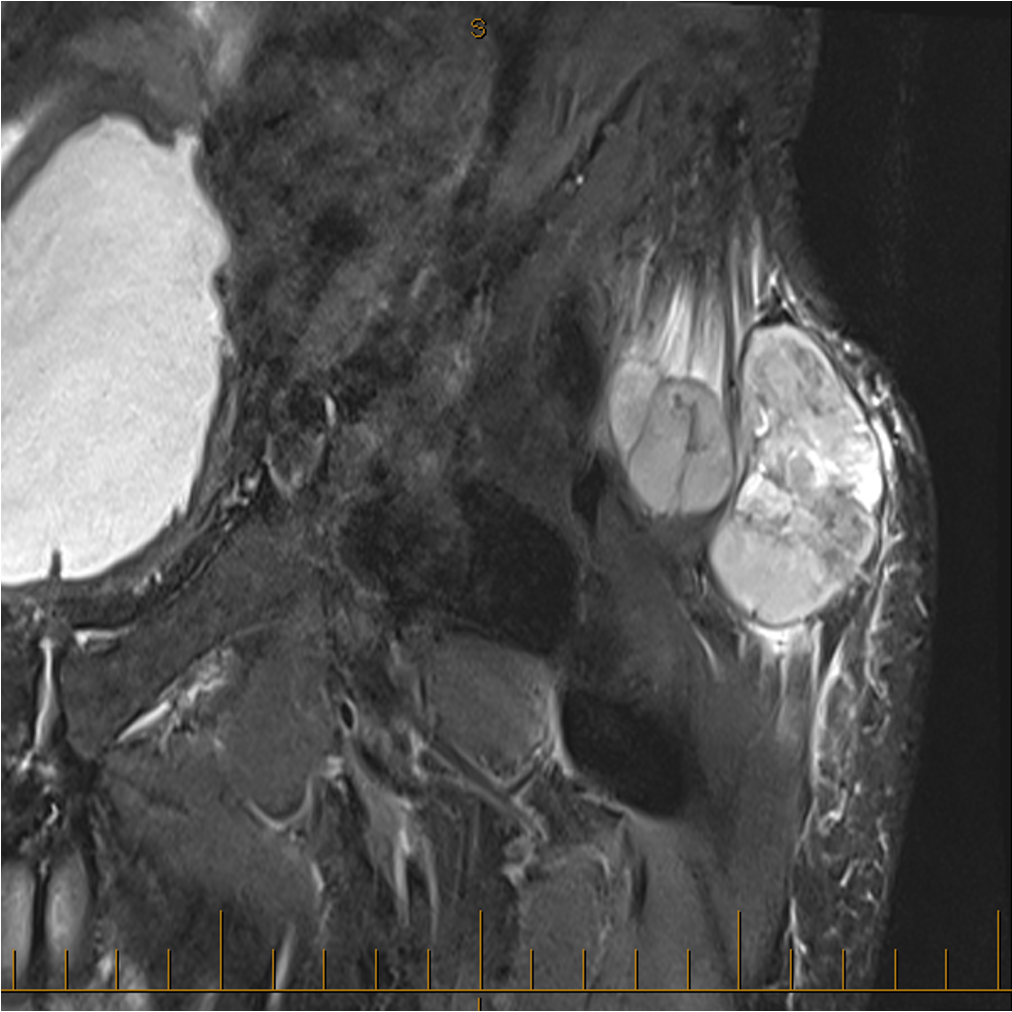

MRI

Anatomy / neurovascular involvement

Sarcoma medial thigh

Sarcoma anterior thigh

Sarcoma posterior thigh

Sarcoma buttock

Sarcoma knee

Superficial tibial sarcoma

Forearm sarcoma